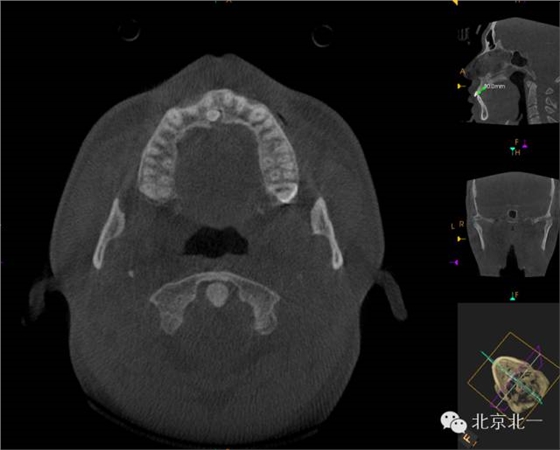

CBCT顯示埋伏多生牙位于腭側(cè)高位,接近切牙管開口位置。

CBCT冠狀位顯示多生牙位于鼻腭神經(jīng)管